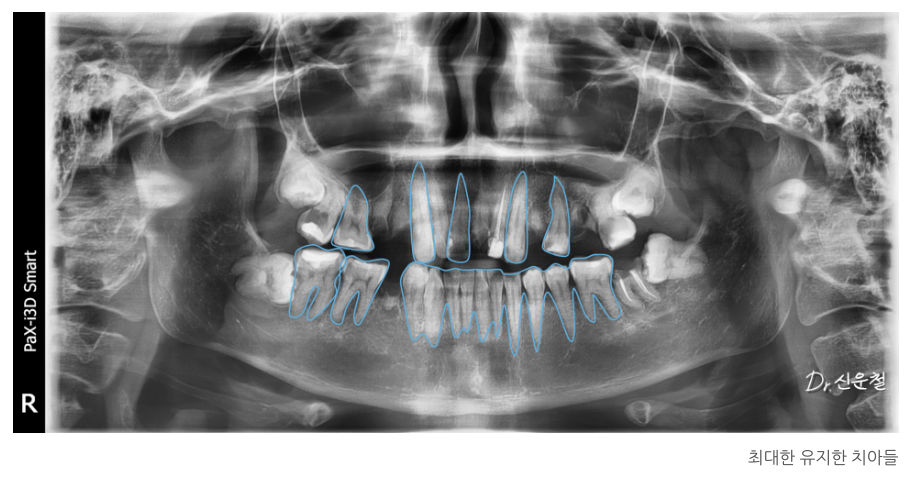

진단 결과

여러 부위의 충치와 결손치,

그리고 임플란트가 필요한 부위가 확인되었습니다.

2차 치료: 남아 있는 치아는 최대한 보존